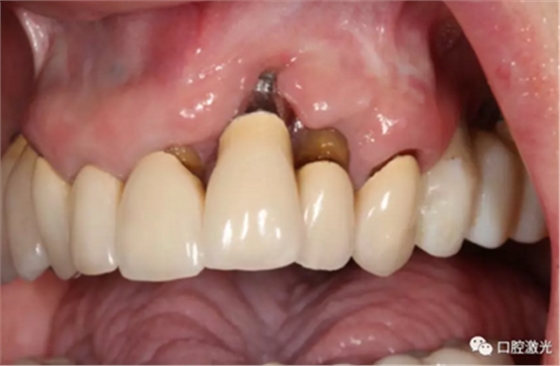

激光非手术种周炎治疗前与治疗后2年的对比